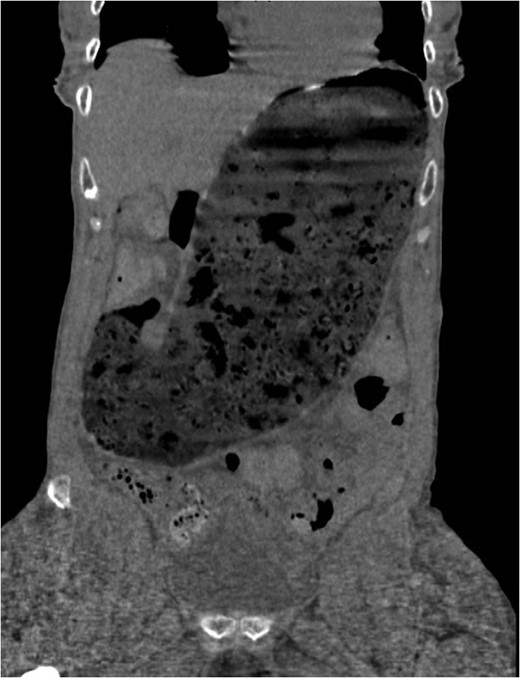

A 63-year-old cachectic female with a medical history of multiple myeloma and advanced amyloidosis was admitted to our institution with complaints of left lateral thigh pain and nausea. At the time of presentation, her myeloma and associated vertebral fractures were under active treatment with cyclophosphamide and bortezomib. Ibuprofen had been prescribed 10 days prior to admission for musculoskeletal pain. The patient’s nausea was associated with increasing abdominal distention over approximately 3 months. Computerized axial tomography performed on admission (Fig. 1) demonstrated a dilated stomach containing fecalized material. The patient reported passing gas and stool. She was placed on a general diet and was managed without nasogastric decompression as per her medical team. She continued to receive ibuprofen and was treated with pulse dose steroids, cyclophosphamide and bortezomib until hospital day 5 when the patient complained of sudden, severe abdominal pain.

Computed tomography scan at presentation (prior to perforation) demonstrating gastric distention secondary to amyloid provoked gastroparesis with fecalization of gastric contents.